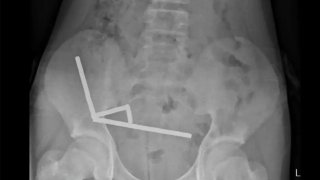

ประวัติศาสตร์การปักปันเขตแดนไทย-กัมพูชา